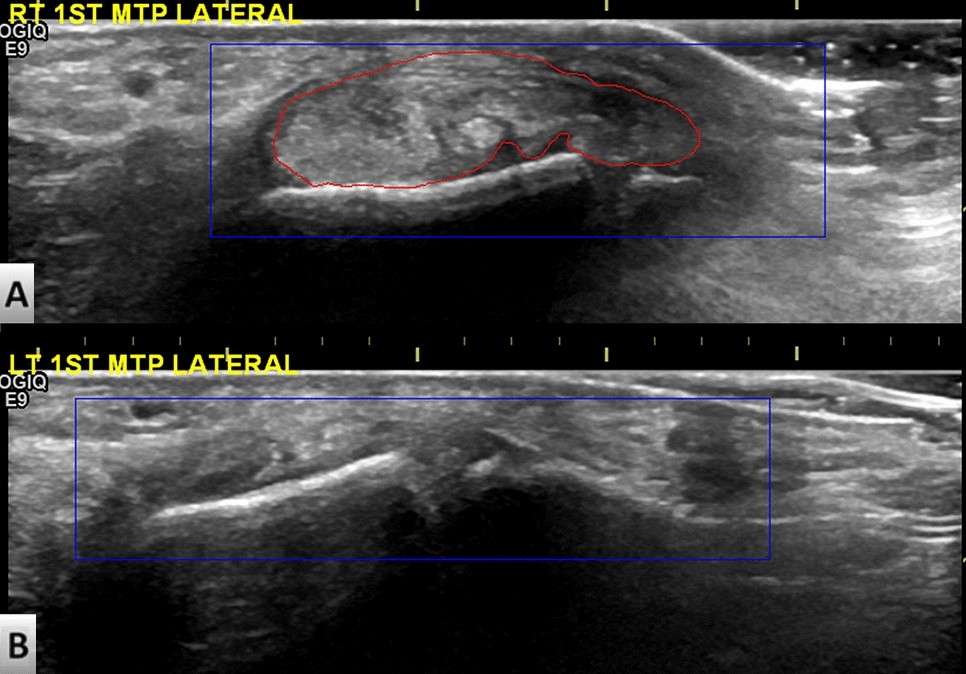

Ultrasound images of (A) left 1st metatarsophalangeal joint lateral side with tophi and (B) right 1st metatarsophalangeal joint lateral side without tophi in single gout patient. The red curve indicates the boundary of the tophi region. The blue rectangle frame indicates the region of interest drawn by a rheumatologist for subsequent transfer learning.